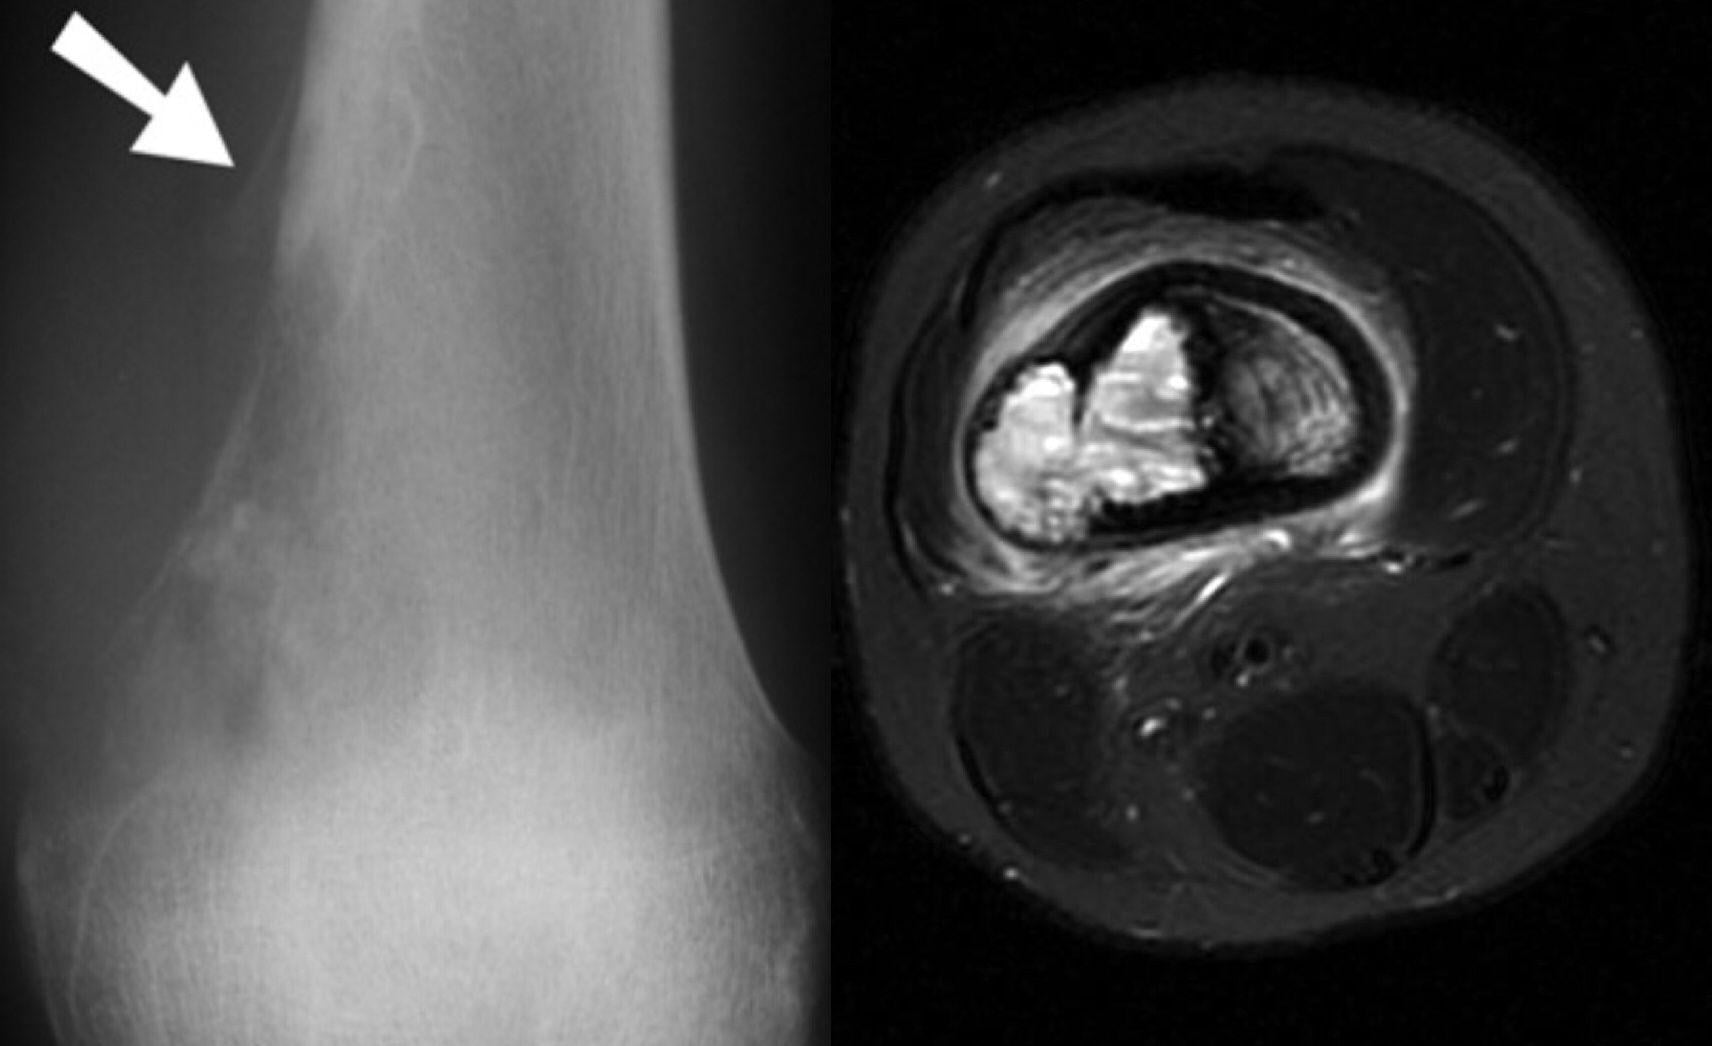

當臨床檢查懷疑是骨腫瘤,骨科醫生會立刻安排患者照X光。假如照出骨骼出現病變,就需要加上電腦掃描、磁力共振以至於正電子掃描,以評估骨腫瘤是良性或惡性,惡性腫瘤屬原發性或更常見的癌症骨轉移。除了影像檢查外,抽取活體組織來化驗,對於確診腫瘤類型,並計劃治療方案至為關鍵。

治療需要骨科腫瘤科及臨床腫瘤科共同協作,通常需要結合手術、化療及電療。手術旨在切除骨腫瘤的同時,盡可能保留正常組織,再植入金屬假體來取代移除的骨骼。但在某些情況下,例如是腫瘤已侵蝕至主要血管及神經,患者便唯有接受截肢來保命。化療和電療,通常用於術前縮小腫瘤及阻止癌細胞擴散至全身,以增加切除的成功率,並在術後消滅殘留的癌細胞,以降低復發率。